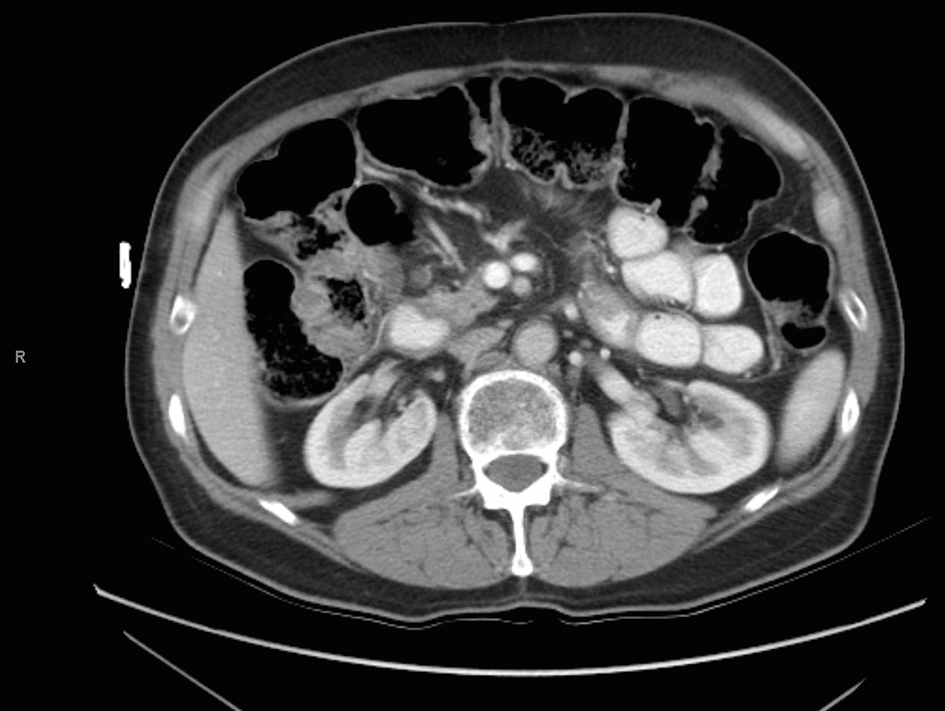

A 73-year-old male with a history of palliative choledochojejunostomy for unresectable pancreatic adenocarcinoma 8 years prior presented to our emergency department with a 2-day history of vague abdominal pain, malaise and subjective fevers. Laboratory testing demonstrated an elevated white blood cell count of 13.9 × 103/μL (reference range 3.7 - 8.4 × 103/μL) and normal liver function tests and chemistry panel. As part of his diagnostic workup, a CT scan of the abdomen and pelvis was obtained, which demonstrated diffuse thickening of the hepaticobiliary limb concerning for a functional afferent limb syndrome due to bacterial overgrowth (Fig. 1). The patient was admitted to the surgical care unit and treated with a course of levaquin and flagyl. His symptoms and leukocytosis quickly resolved and he was discharged to home on hospital day 2.

![]() Click for large image | Figure 1. CT scan for evaluation of abdominal pain 8 years after diagnosis of pancreatic cancer demonstrating functional afferent limb syndrome. |